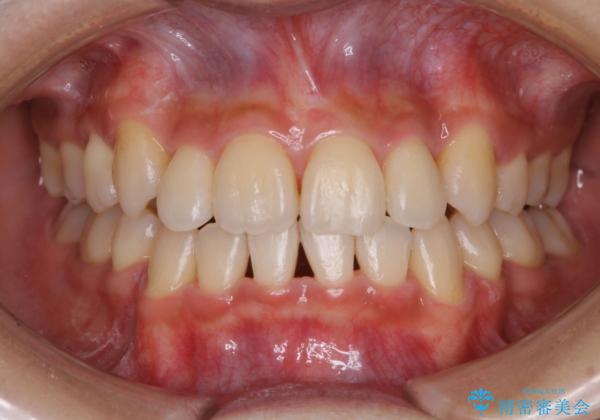

PMTC60分コースを行いました。紅茶による着色が全体的に付着していました。

インビザライン中の患者様で、紅茶を飲んだ後にそのままマウスピースをはめていたそうです。着色が、かなり目立っていた為、追加アライナーのタイミングで全体の着色を除去し、とても綺麗になりました。